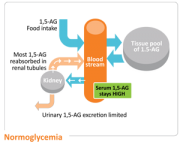

| 18:30, 12 באוקטובר 2017 | GlycoMark3.jpg (קובץ) |  |

17 קילו־בייטים | Motyk | 1 | |

| 18:28, 12 באוקטובר 2017 | GlycoMark2.png (קובץ) |  |

31 קילו־בייטים | Motyk | 1 | |

| 18:27, 12 באוקטובר 2017 | GlycoMark1.png (קובץ) |  |

29 קילו־בייטים | Motyk | 1 | |

| 18:25, 12 באוקטובר 2017 | GlycoMark.png (קובץ) |  |

12 קילו־בייטים | Motyk | 1 | |